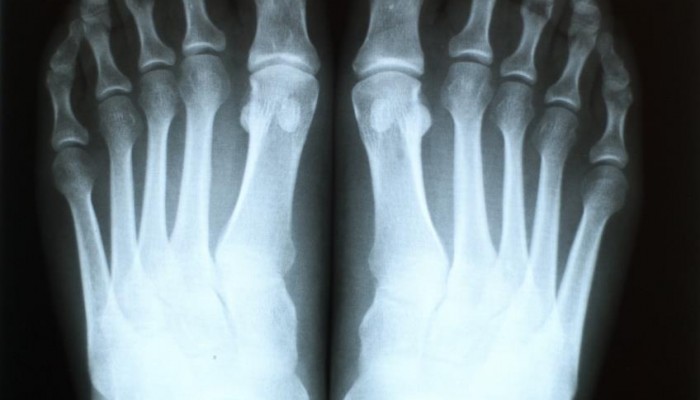

Рентгенография

При хронической форме проводят рентген. На ранних сроках подагры (приблизительно 1 год с начала болезни) не делают потому, что на снимке изменения не будут видны.

Что показывает рентген при хронической подагре:

- В субхондральных костях обнаруживаются тофусы. Иногда в мягкой ткани можно увидеть уплотнение.

- На поверхности сустава мелкая киста, крупная эрозия вблизи него. Характерны уплотнения с кальцификатами поблизости сустава.

- Эпифиза остеолиз; обширная эрозия, которая затрагивает 1/3 сустава; уплотнение с известью.

Литические эрозии являются признаком и других болезней: амилоидоза, гиперлипопротеинемия IIA типа, мультицентрический ретикулогистиоцитоз. Поэтому врач обращает внимание на такие детали:

- Размер суставной щели (при подагре 69,70).

- Периартикулярная остеопения (должна отсутствовать).

- Располагается поза суставной капсулы.

Подагрические эрозии, как правило, локализуются недалеко от дистального сустава, распределение должно быть асимметричным. Кроме того, присутствует склеротическая граница.